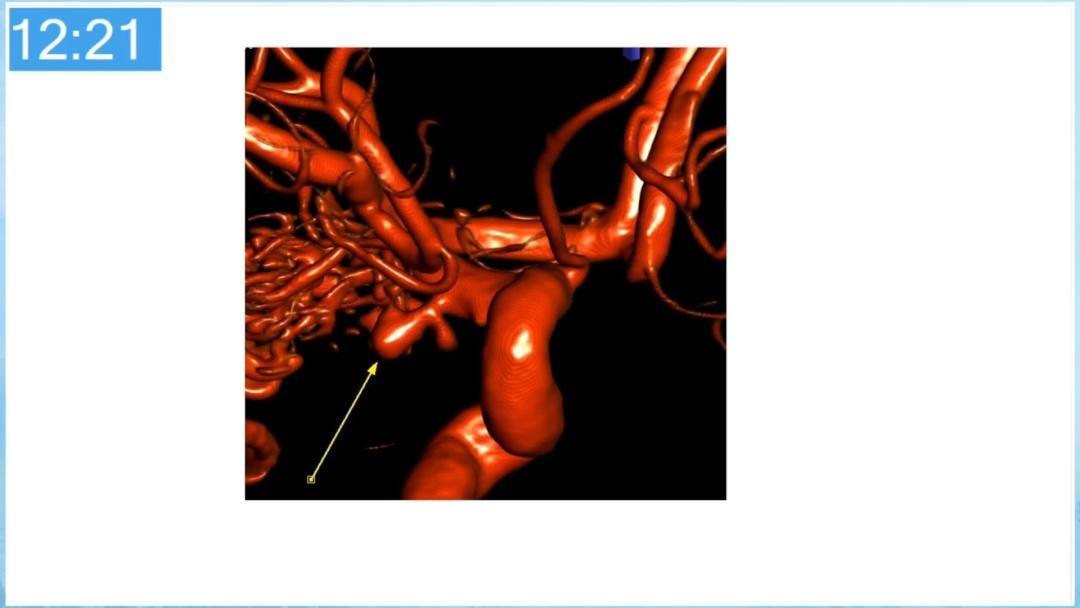

合理的复合平台下的综合治疗,针对每一个病变对应不同方法安全性分析,不预设、不排斥,每种技术发挥到最佳,互相保障。

本期为大家特别分享:空军军医大学唐都医院邓剑平教授的精彩会议内容《颅内动静脉畸形的复合手术治疗》,欢迎大家阅读和分享!